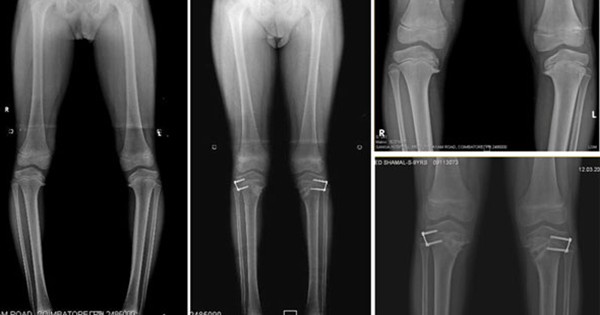

Các kỹ thuật hình ảnh như chụp X-quang và MRI , siêu âm và CT cũng có thể giúp chẩn đoán.